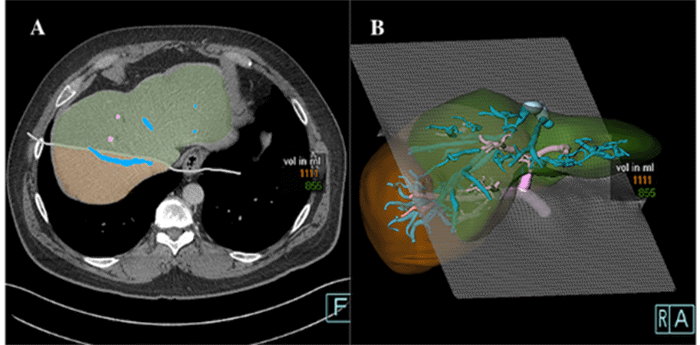

Figure 3. Three-dimensional CT Volumetry Reconstruction of Planned RPS Liver Graft. Published with Permission

Estimated graft volume of 1111 cc using a plane along the right hepatic vein for transection

Fortunately, a potential living liver donor was identified. Donor liver MRI revealed acceptable steatosis but unusual biliary anatomy with five bile ducts converging at the confluence. Donor protocol CT demonstrated a Nakamura type D portal vein configuration10 (Figure 2A, 2B). The anterior sector of the donor's liver was supplied by a branch of the left hepatic artery running within the same portal pedicle as the right anterior sector portal vein (Figure 2C, 2D). Estimated volumes of the posterior segment graft (1111 cc) and the donor remnant liver (855 cc) were obtained (Figure 3A, 3B).

RPS volumetry can be less reliable than whole lobe volumetry due to the lack of consistent anatomical landmarks beyond the right hepatic vein, leading to potential overestimation (approximately 19%).8 In our case, the estimated RPS graft volume by CT volumetry was 1111 cc, while the actual graft weight was 740 g, representing a discrepancy of nearly 37%.